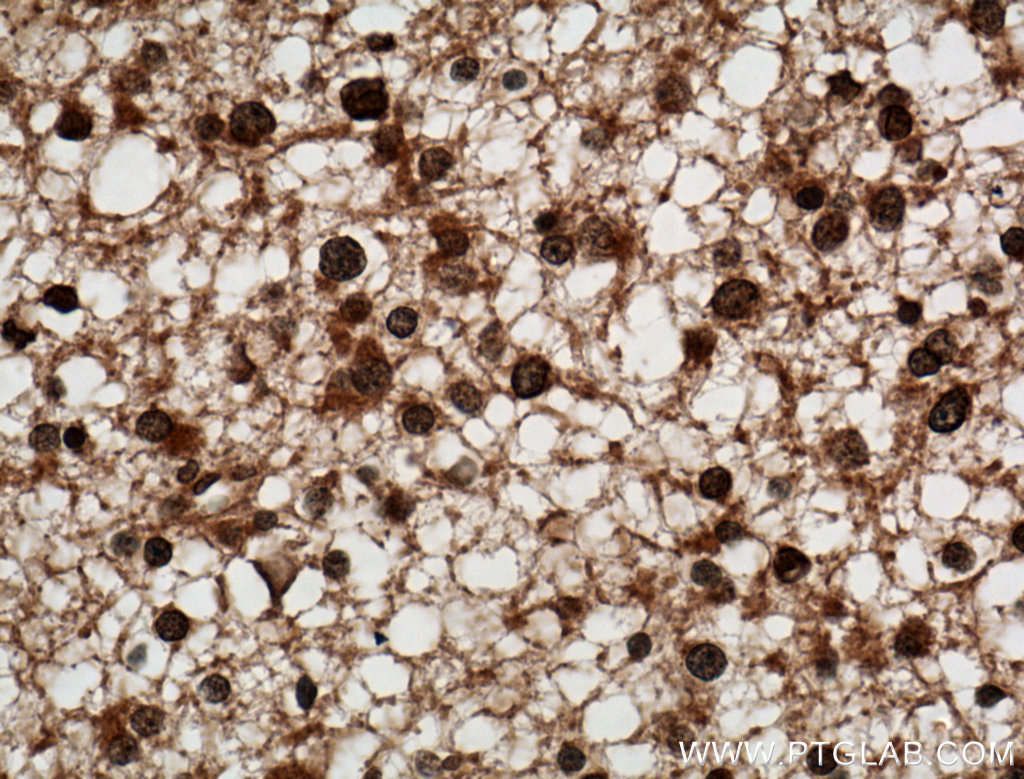

Immunohistochemical analysis of paraffin-embedded human gliomas tissue slide using 66140-1-Ig (C9orf72 antibody) at dilution of 1:1000 (under 40x lens) heat mediated antigen retrieved with Tris-EDTA buffer(pH9). |